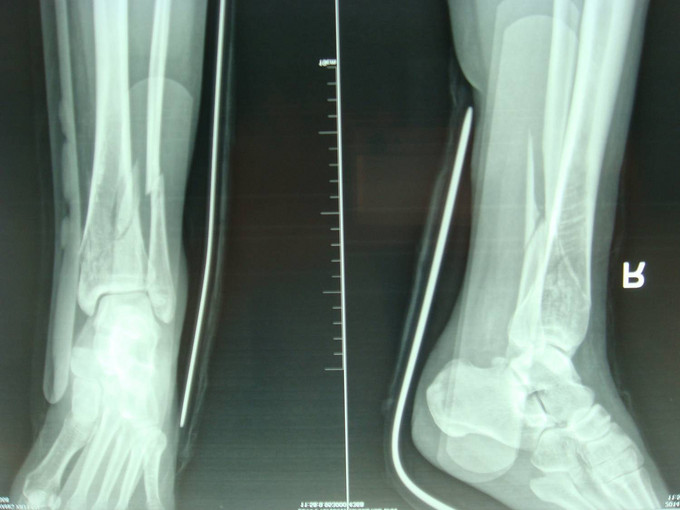

主诉:右小腿外伤后6天 现病史:患者2014-10-19日晚9时左右下楼时不慎摔倒,后于骨科医院就诊,行右下肢DR检查,提示右胫腓骨远端粉碎性骨折,后患者于骨科医院行夹板固定,并与当地祝家镇诊所输液治疗,具体治疗方案不详。后患者为求进一步诊治逐来我院。并以右胫腓骨远端粉碎性骨折收入院。患者病来一般状态可,二便正常,饮食睡眠可。

诊断:右胫腓骨远端粉碎性骨折 患者为右plion骨折,入院后局部肿胀明显,给予患肢抬高,冷敷,消肿等对症治疗,密切观察患肢皮肤情况,带皮肤条件良好的情况下,约2周后行右三踝骨折切开复位钢板内固定术。